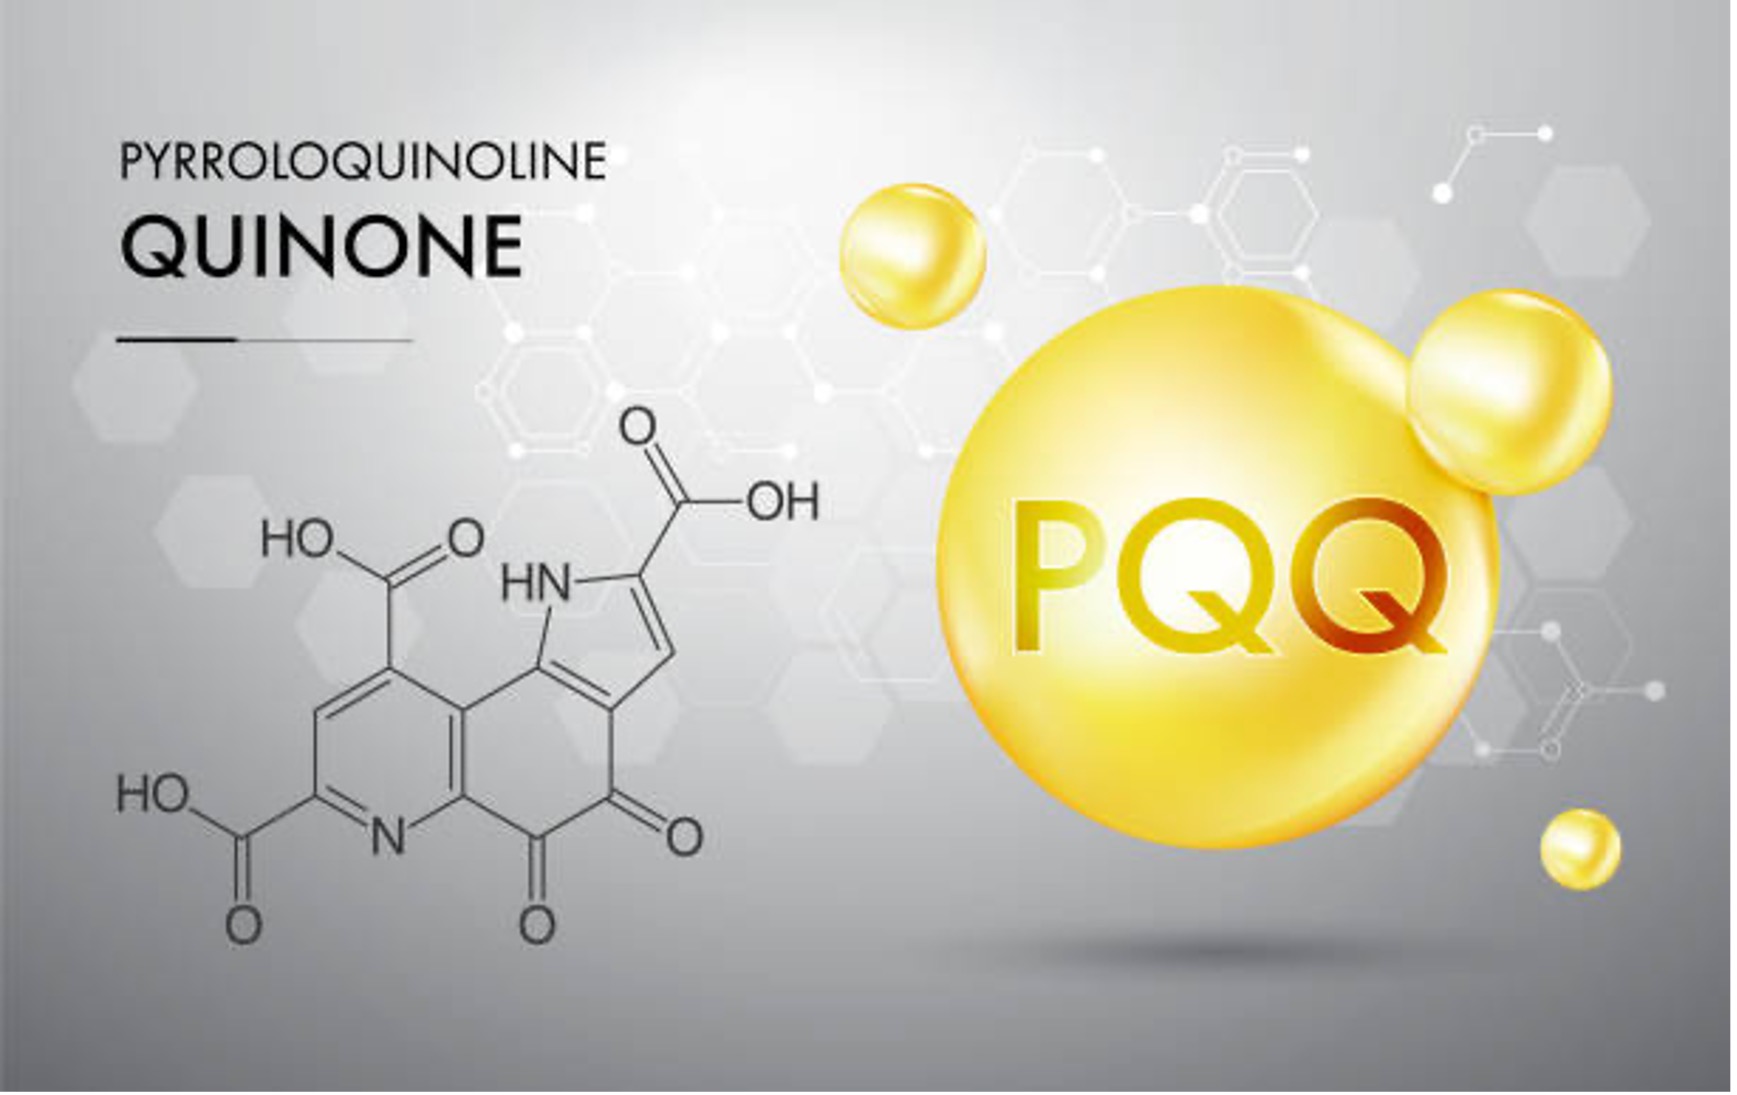

骨骼營養補充怎麼選?不只是補鈣而已

許多人補鈣卻效果有限,關鍵在於:

鈣吃進去 ≠ 鈣進骨頭

真正影響骨密度的是「鈣能不能被吸收、能不能進到正確的位置」。

骨骼營養的黃金組合

- 鈣:骨骼的原料

- 維生素 D3:幫助鈣吸收

- 維生素 K2:引導鈣進入骨骼、避免沉積在血管